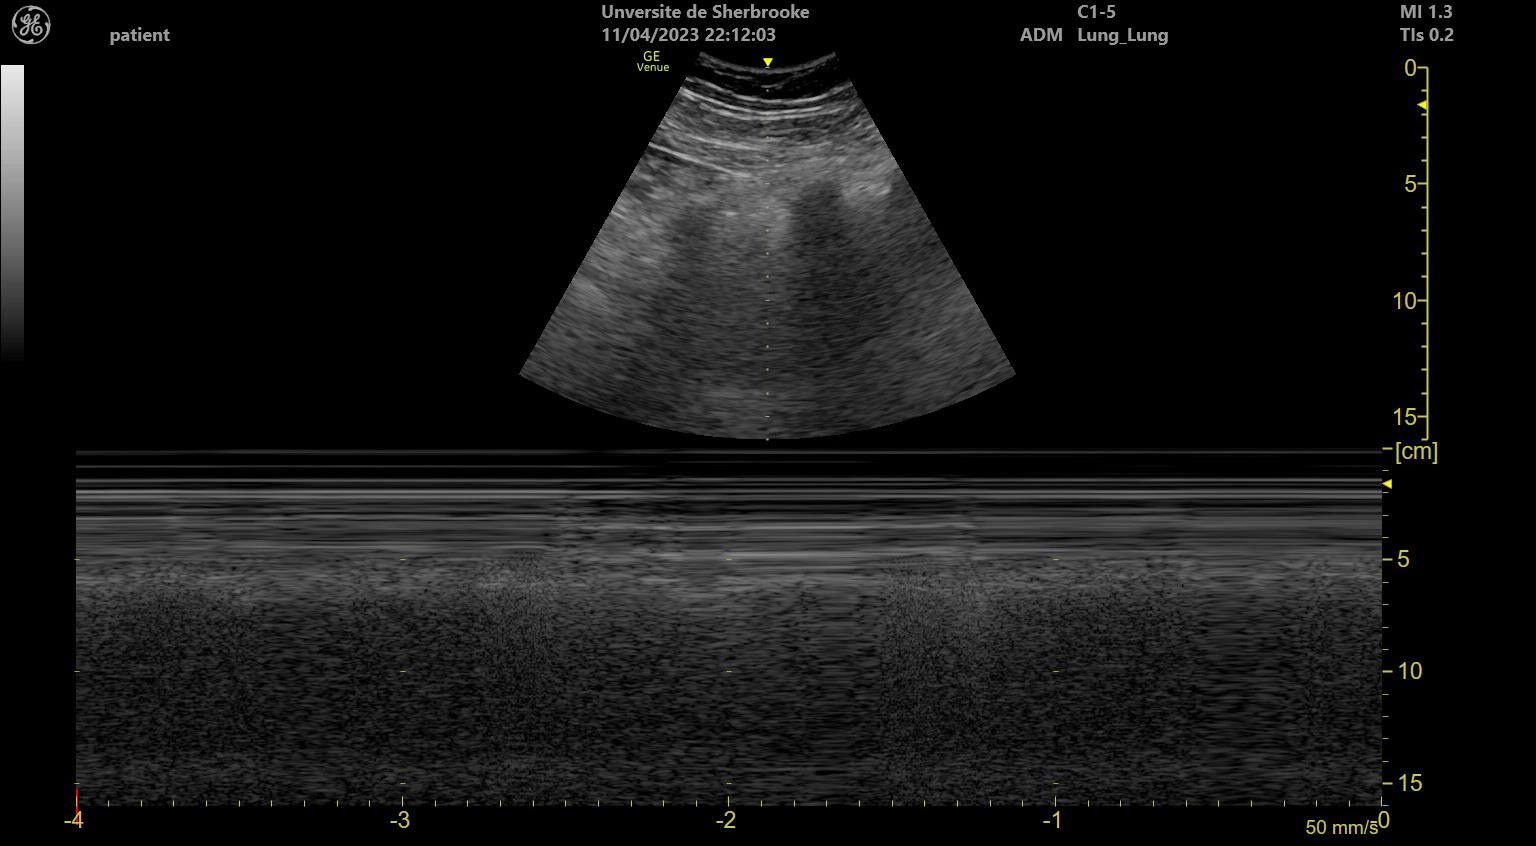

Der Pneumothorax im Ultraschall#

Der Ultraschall eignet sich auch sehr gut zur Diagnostik des Pneumothorax. Hierbei ist zu beachten, dass man den Pneumothorax selber nicht direkt darstellen kann, sondern sich indirekter Zeichen bedient. Weiter ist der Ultraschall eine punktuelle Diagnostik, folglich muss die Ultraschall-Evaluation an verschiedenen Stellen des Thorax durchgeführt werden, um eine Übersicht und eine Aussage zu ermöglichen.

M-Mode:

• Seashore Sign ist der Normalbefund, die atmungsbedingten Artefakte erinnern an einen Sandstrand.

• Fehlen diese atmungsbdingten Lungenbewegungen zeigen sich im M-Mode statische Echo, welche über die Zeit als gerade Striche aufgetragen werden. Da dies an einen Strichcode erinnert, wird dieses Zeichen Barcode Sign genannt.

../../../_images/Sea_shore_sign_on_a_lung_ultrasound.jpg

Fig. 111 Das Seashore Sign im M-Mode ist ein Normalbefund, die atmungsbedingten Bewegungsartefakte erinnern an einen Sandstrand. [© Tinss, ℓ CC BY-SA 4.0]#

../../../_images/Barcode-Zeichen.jpg

Fig. 112 Barcode Sign im M-Mode: Die aufgrund des Pneumothorax unbewegten Konturen imponieren als Striche wenn die Echos über die Zeit aufgetragen werden. [© Cuprschomynv, ℓ PD]#